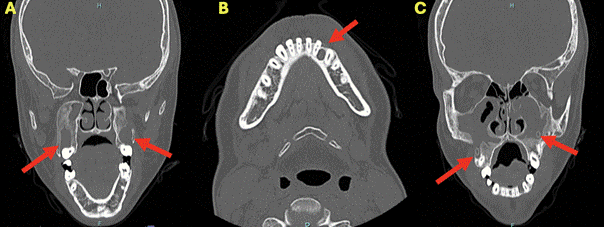

Paciente sexo masculino de 19 años, derivado en el año 2021 desde un recinto hospitalario pediátrico con diagnóstico de SGG para el abordaje terapéutico de los QO de los huesos maxilares por el equipo de Cirugía Maxilofacial del Hospital San José. Al examen clínico presentaba cánulas de tratamiento descompresivo para múltiples QO diagnosticados con anterioridad en el recinto hospitalario de origen. El tratamiento había sido iniciado en 2019 y se continuó hasta el 2021, consiguiendo la disminución de tamaño de los QO para su posterior tratamiento quirúrgico (Figura 1).

Figura 1. Tomografía computarizada del año 2021, se evidencian tres lesiones hipodensas señaladas con una flecha roja. (A) Dos lesiones hipodensas bilaterales de apariencia quística ubicadas en relación a ambos senos maxilares. (B) Presencia de lesión hipodensa de apariencia quística en zona parasinfisiaria izquierda. (C) Cánulas instaladas en ambas lesiones maxilares.